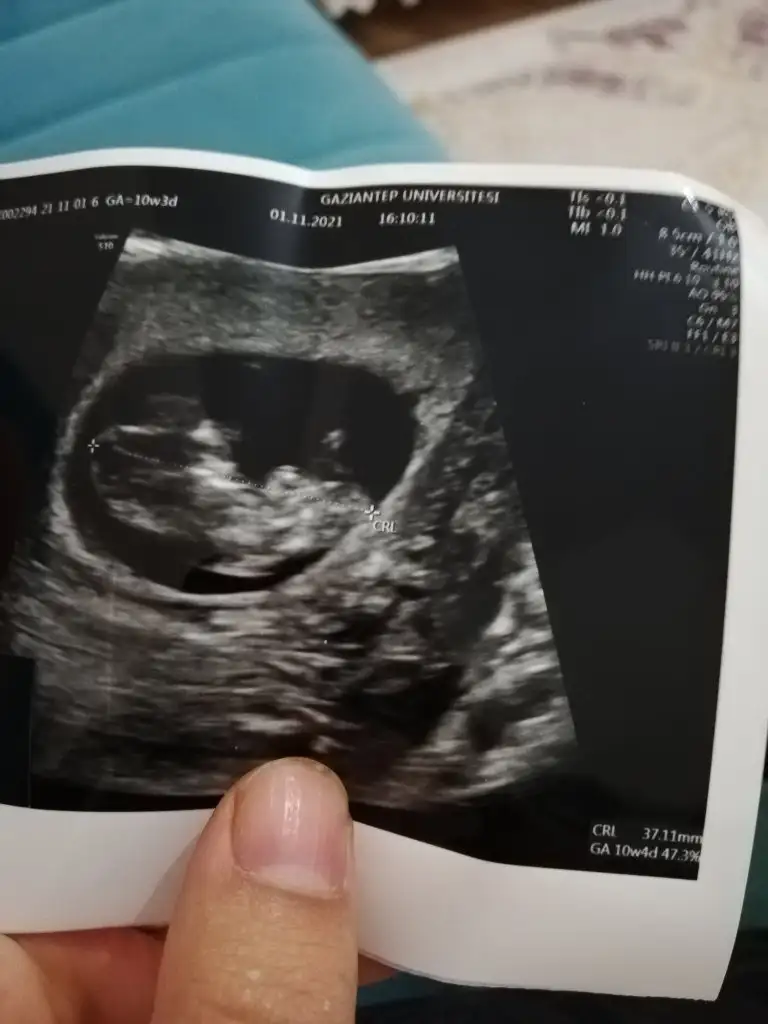

Erkek sankiİkra hanım merhaba 12 hafta görüntülerini ekledim sizce nedir cinsiyeti

Erkek ve kız için 11 + 12+ yada 13 hafta usg görüntüsü olmalı açıklamalar asagıda yazıyorrabbim herkesin gönlüne göre nasip etsin inşallah .. ecmain

[/B]Eki Görüntüle 473828 gordugunuz gibi ust taraftaki simgedende anlasildigi gibi eger cikinti paralel ise kiz

yok 30°lik bir aciyla yukari dogru bakiyorsa %99 oglunuz olacak demektir simdi bi kac ornek resimler daha koyacagim kiziminkide dahil

Eki Görüntüle 473829 bu bir erkek bebek genital nub cikintisi gayet yukarda